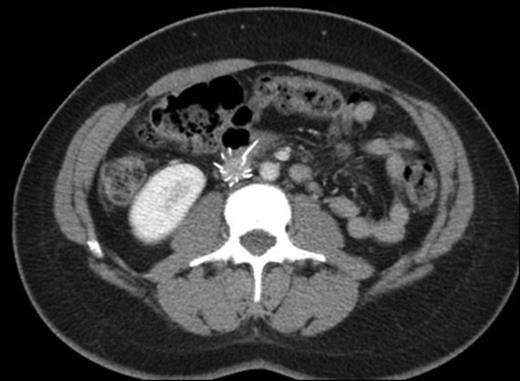

Results: (i) Case Description: A 38-year-old woman with a history of recurrent VTE presented with severe abdominal pain. Her initial left popliteal vein thrombosis and PE had occurred in 2000 after a few months on oral contraceptives (OC). She was treated with warfarin for a year. A recurrent unprovoked episode of left iliofemoral DVT was diagnosed four years later, at which time she was off OC. Indefinite warfarin treatment was started, given her young age and recurrent VTE. She became pregnant two years later and was switched to enoxaparin until two months after delivery. However, she did not restart warfarin and experienced no complications until three years later, when a prophylactic temporary IVC filter was placed prior to partial hysterectomy for menorrhagia. The surgery was performed without complications, but six months later she developed a recurrent untriggered right femoral DVT and began to experience sharp pains and an abrupt change in her bowel habits. At presentation, a CT scan (below) determined that her IVC filter had migrated out of position with its wires protruding into her aorta and spine and perforating her duodenum. Major abdominal and vascular surgery was performed to remove the filter. A thrombophilia panel returned with normal results. The patient was started on rivaroxaban indefinitely with no further issues.

Axial contrast-enhanced CT showing migrated anterior arm of IVC filter protruding into the duodenum.